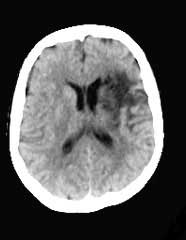

Bei der Computertomografie handelt es sich um ein spezielles Röntgenverfahren, das Querschnittsbilder verschiedener Körperabschnitte anfertigt. Das Verfahren wurde 1972 von dem amerikanischen Physiker A.M. Cormack und dem britischen Ingenieur G.N. Hounsfield entwickelt, die für ihre Entwicklung 1979 den Nobelpreis für Medizin erhielten. Die Methode wurde innerhalb weniger Jahre zum wertvollsten diagnostischen Verfahren der Radiologie.

Mittels einer Röntgenröhre und Blenden wird ein schmaler Röntgenstrahl (Fächerstrahl) erzeugt. Dieser durchdringt die gewünschte Körperstelle und wird innerhalb des Körpers durch die verschiedenen Strukturen (z. B. Haut, Fett, Muskel, Organe, Knochen) unterschiedlich in unterschiedlichem Maße abgeschwächt. Genau gegenüber der Röntgenröhre befindet sich eine Vielzahl von Sensoren (Detektoren), die das abgeschwächte Signal empfangen, elektronisch aufbereiten und einem Computer zur Auswertung weiterleiten. Die einzelnen Gewebe stellen sich unterschiedlich (in Grauabstufungen) Im Anschluss daran dreht sich die Röntgenröhre samt gegenüberliegenden Detektoren geringfügig um den Patienten weiter. Der beschriebene Vorgang wiederholt sich. Auf diese Weise werden verschiedene Ansichten (Projektionen) derselben Schicht erzeugt und im Computer zu einem Graustufen-Bild umgerechnet.

Im Vergleich zum üblichen Röntgenbild ist das CT-Bild übersichtlicher, da der Arzt dank der besseren Kontrastabstufung zwischen den verschiedenen Gewebearten wie Knochen, Muskel oder Fett unterscheiden kann. Dieser Umstand kann durch Spritzen oder Trinken von Kontrastmitteln noch verbessert und optimiert werden.

Ein weiterer Vorteil ist, dass das CT-Bild kein Überlagerungsbild darstellt, wie es beim normalen Röntgenbild der Fall ist. Beim CT wird also nur eine Schichtebene abgebildet, die dementsprechend nicht von anderen Schichten überlagert wird. Zudem gibt es die Möglichkeit, mit Hilfe eines Computers ein dreidimensionales Bild zu erzeugen.

Gegenüber dem herkömmlichen Röntgenbild hat die Computertomografie allerdings einen Nachteil: Die räumliche Auflösung ist schlechter. Daher sind die Knochenstrukturen im CT weniger gut erkennbar. Wichtig für Kontrolluntersuchungen im Rahmen der Neurofibromatose ist wohl vor allem die craniale Computertomografie (Tomographie des Kopfes, CCT).